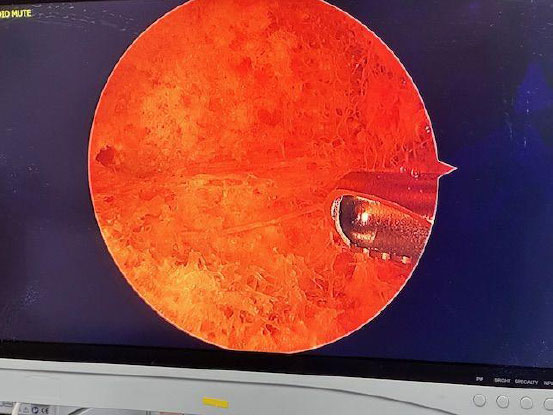

The femoral neck intramedullary cavity was large and easily visualized using standard arthroscopic tools (Fig. 3a, b – cavity and 3.5 mm shaver for scale). The cavity measured approximately 3 cm medial-lateral and 2.5 cm superior-inferior.

Arthroscope and shaver in place under fluoroscopy.

Cavity and 3.5 mm shaver for scale.

On entry, fibrofatty tissue and cancellous bone were visible (Supplementary Video 1) and easily removed with irrigation and gentle debridement (Supplementary Video 2). The inferior portion of the femoral neck appeared softer than the superior portion when probed. A clear transition was seen between the hollow femoral neck and the denser femoral head.

Fibrous bands and adipose tissue were present at the medial femoral neck/intertrochanteric junction (Fig. 4). This tissue was removed with ease using the RF probe.

A biportal technique facilitated fluid inflow/outflow, visualization, and working space. Visualization remained unobstructed, and no fluid outflow compromise was noted once triangulation was achieved. Cortical bone thickness appeared unchanged on fluoroscopy post-debridement.